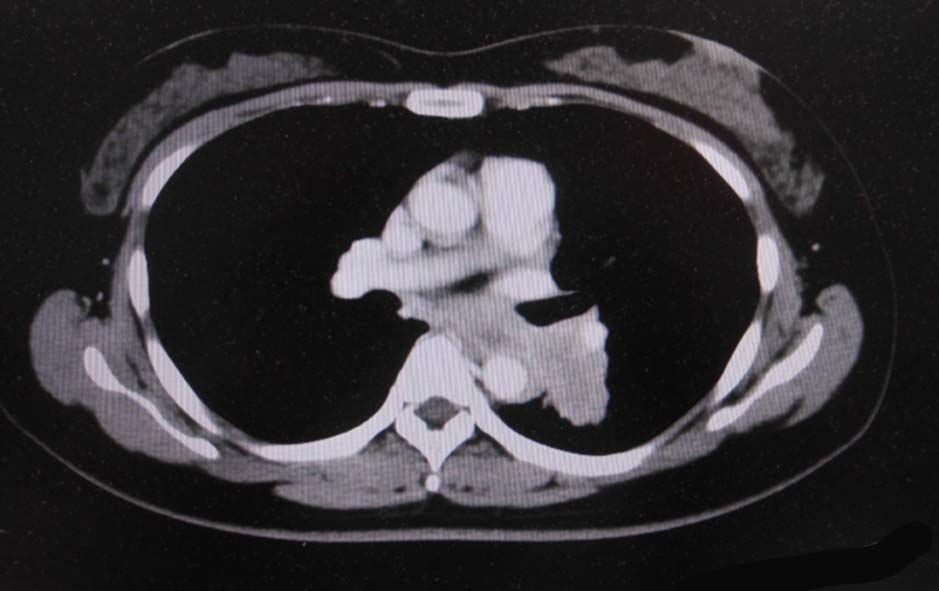

IWT case: 30歳代半ば,女性*2; 喫煙歴:15本/日,20歳から現在まで

当院を受診する4か月前から前胸部違和感を自覚していた. 2か月前から喘鳴を伴う咳嗽があり近医を受診.気管支喘息が疑われ加療されたが症状は改善しなかった.

経過観察中に施行された胸部CTでは左肺癌が疑われた.精査加療目的に当院呼吸器内科を紹介受診.

血液検査:腫瘍マーカー cytokeratin 19の上昇あり[14 (>3.5ng/mL)],ProGRP, CEA, CA19-9の上昇なし

CT画像:左肺から縦隔に及ぶ腫瘍(肺は単独病変. 肺内転移なし.),乳腺腫瘤,子宮腫瘤, 多発肝腫瘤あり.

処置: 気管支内視鏡検査で,1.左肺腫瘍からTBB (VS1),2.腫瘍と一塊になったリンパ節からEBUS-TBNA (VS2),を施行された.

CT画像および肺腫瘤生検組織